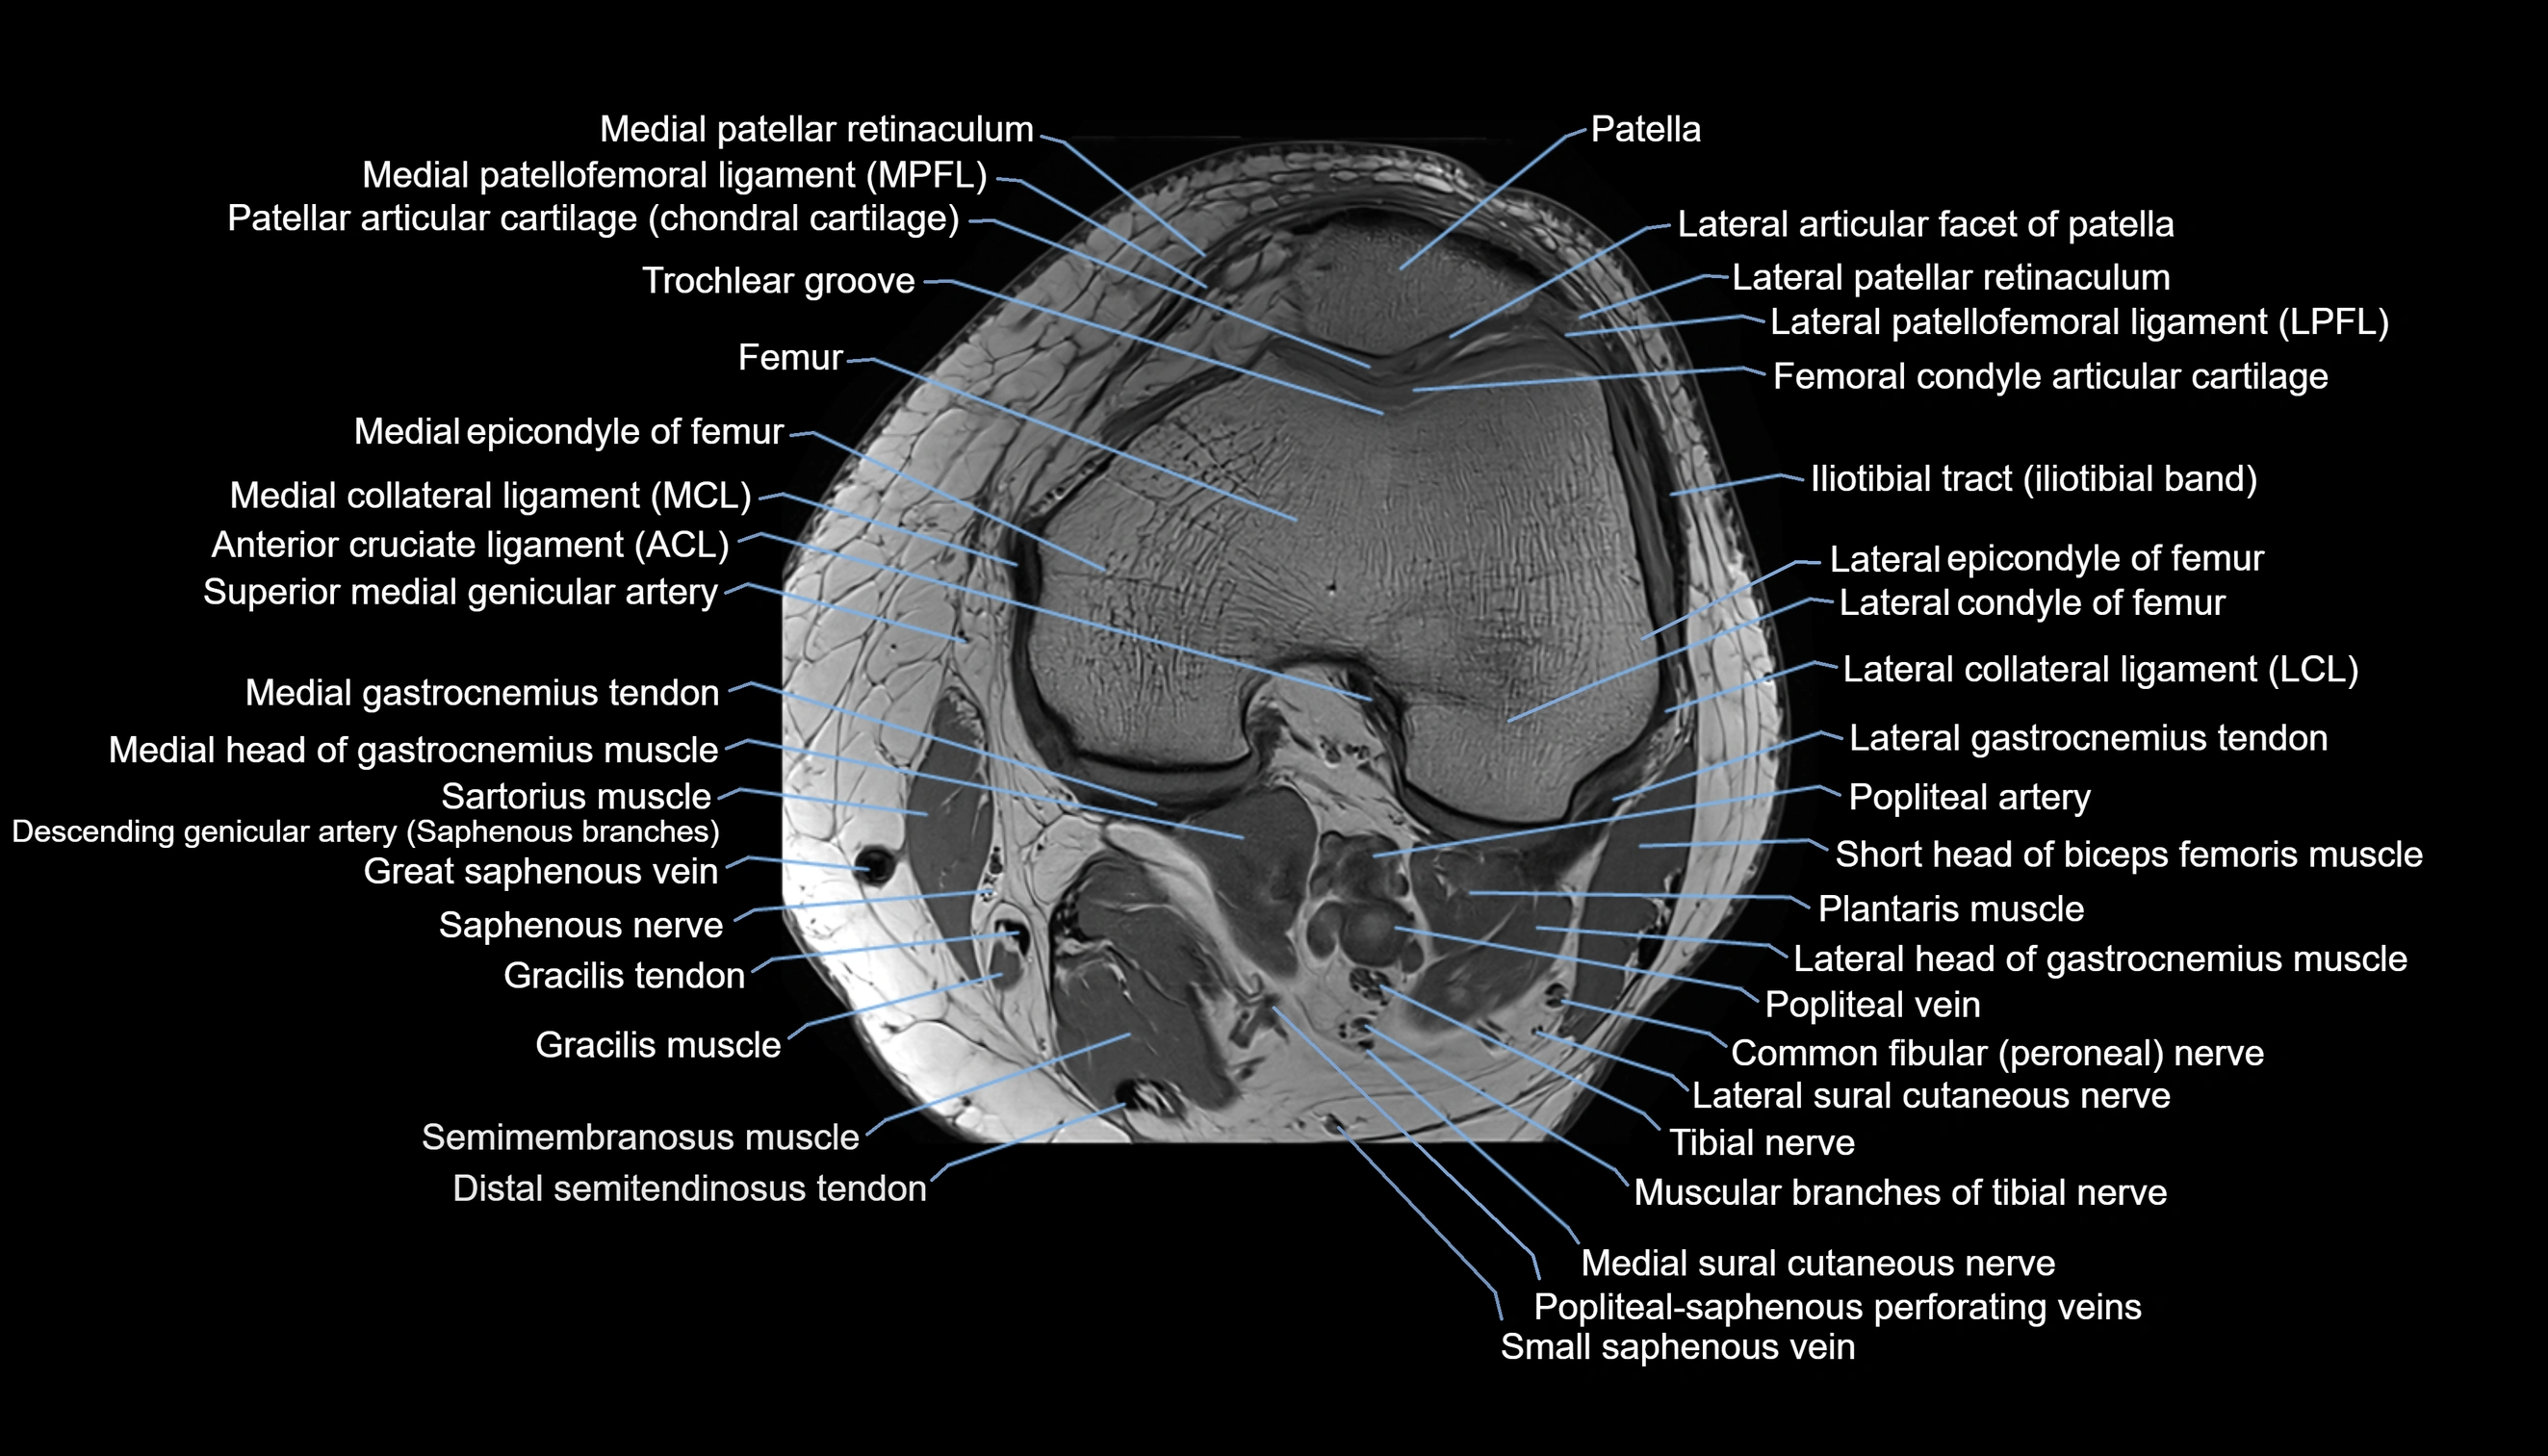

- Common fibular nerve

- Femoral condyle articular cartilage

- Gastrocnemius muscle

- Lateral articular facet of patella

- Lateral collateral ligament

- Lateral condyle of femur

- Lateral epicondyle of femur

- Lateral patellar retinaculum

- Lateral patellofemoral ligament

- Lateral sural cutaneous nerve

- Medial collateral ligament

- Medial condyle of femur

- Medial epicondyle of femur

- Medial gastrocnemius tendon

- Medial head of gastrocnemius muscle

- Medial patellar retinaculum

- Medial patellofemoral ligament

- Medial sural cutaneous nerve

- Muscular branches of tibial nerve

- Patellar articular cartilage

- Popliteal artery

- Popliteal vein

- Saphenous nerve

- Sartorius muscle

- Semimembranosus muscle

- Small saphenous vein

- Soleus muscle

- Superior medial genicular artery

- Tibial nerve

- Trochlear groove